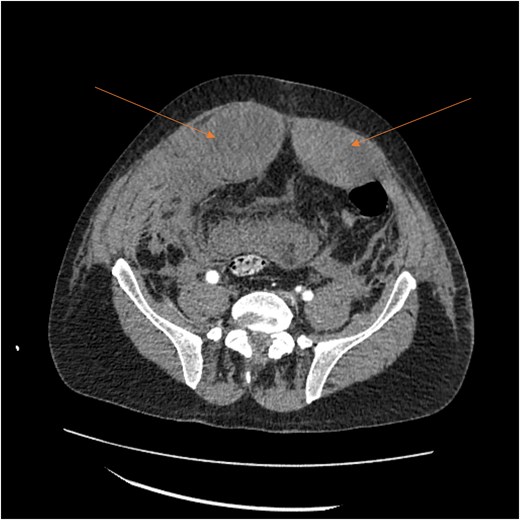

Angiogram of the left inferior epigastric artery (arrow) demonstrating no active bleeding.

A follow-up CT scan performed 2 days after placement of IVC filter and stopping anticoagulation showed further enlargement of the hematoma (17.5 × 14 × 25.7 cm) and ongoing bleeding. Interventional radiology performed bilateral inferior epigastric artery angiograms, which revealed no ongoing artery bleeding but truncation of the right inferior epigastric artery. Empiric Gelfoam embolization was performed on the left inferior epigastric artery (Fig. 4).